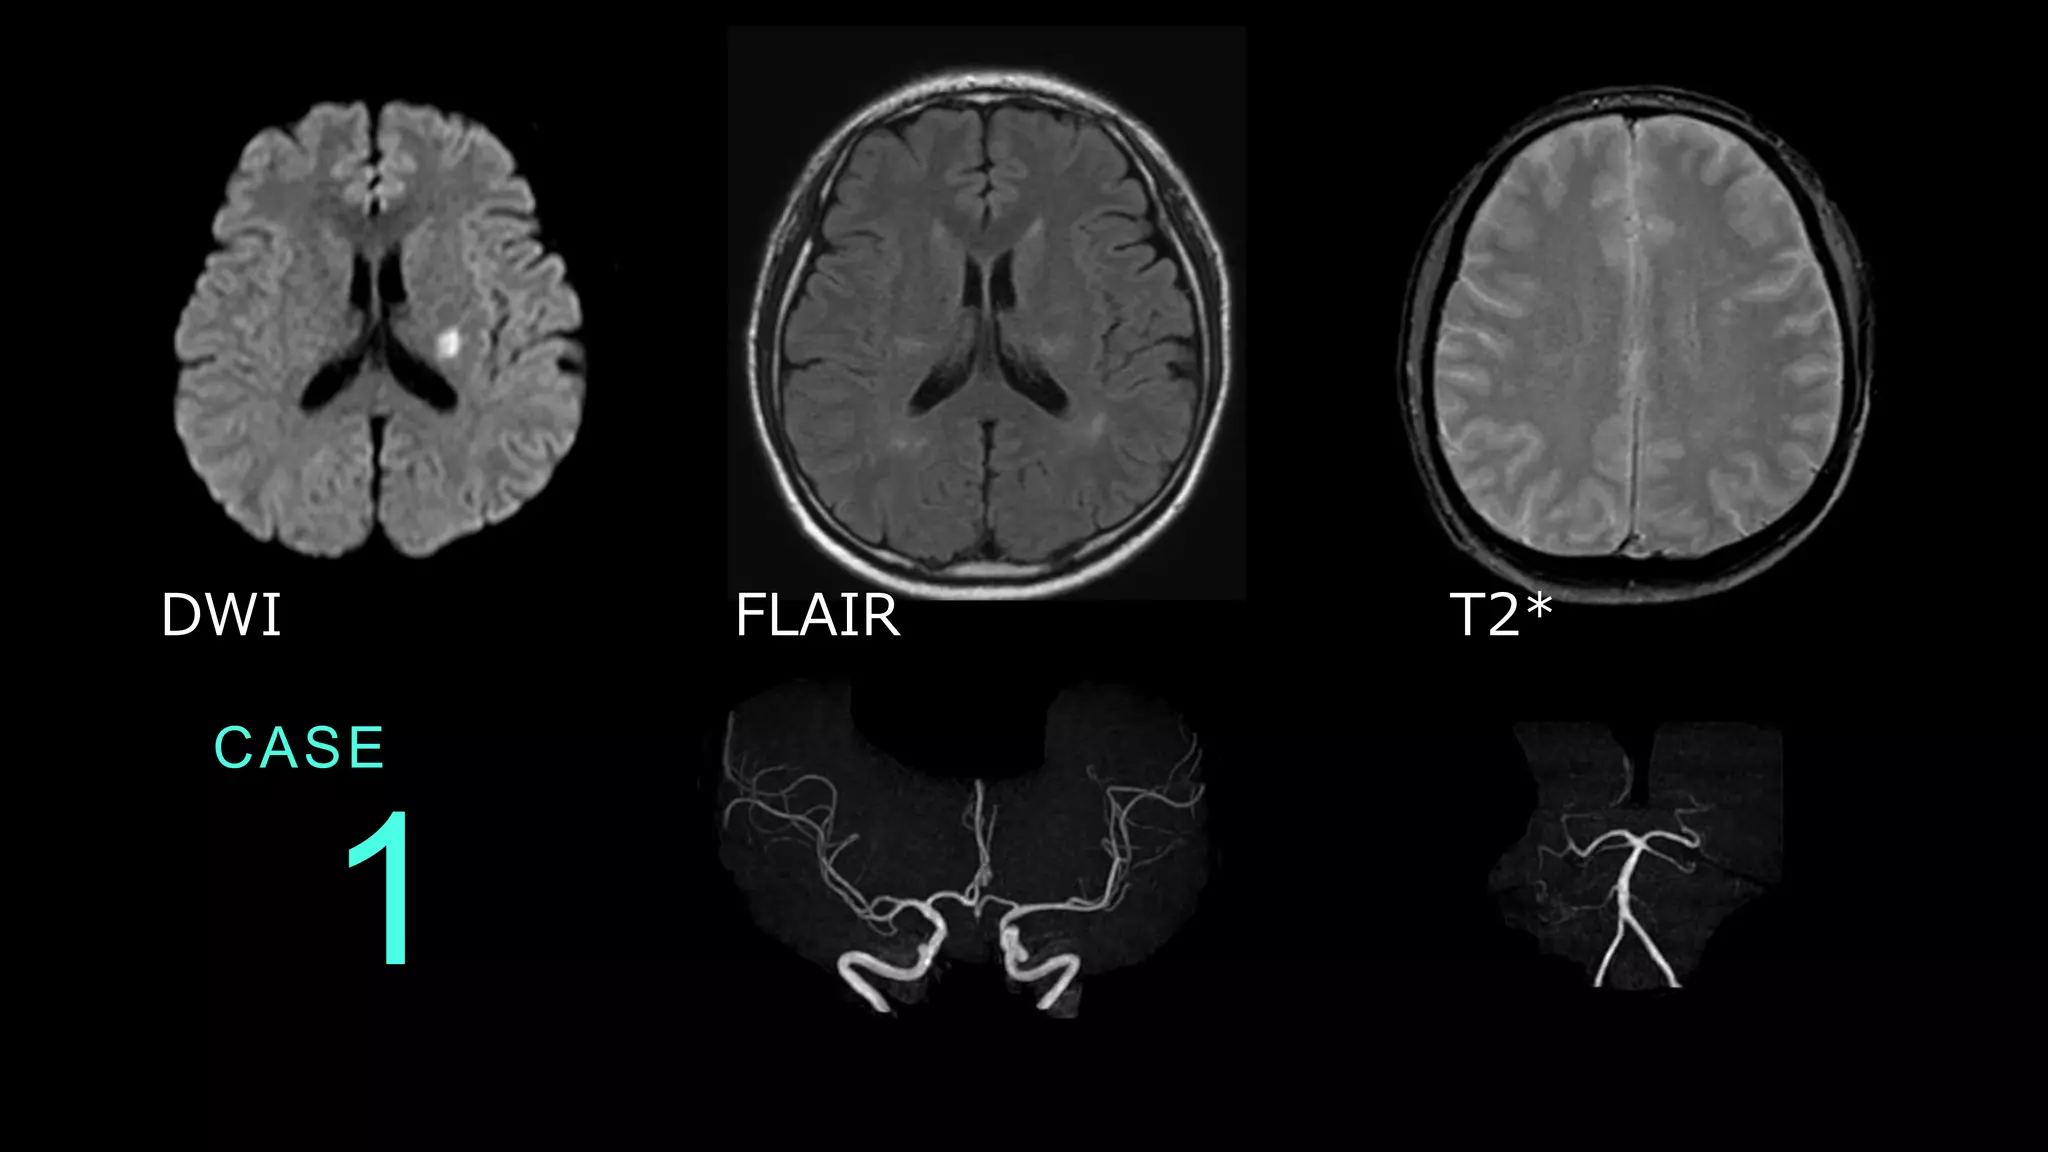

1 CASE DWI FLAIR T2*

1 CASE DWIでは基底核レベルのスライスで左側に高信号病 変を認める。FLAIRでは同病変は等信号である。 T2*ではmicrobleedsは認めない。 DWI FLAIR

1 CASE MRAでは、前方循環系・後方循環系ともに目立った 血管狭窄病変は認められない。

1 CASE コメント: DWI HIGH、FLAIR ISOの信号変化 であり、超急性期の脳梗塞病変です。 左の中大脳動脈(MCA)の穿通枝領域 梗塞。 脳梗塞疑いの場合には、血管支配に一 致した病変であるかどうかを検討して います。 これは典型的なラクナ梗塞画像。